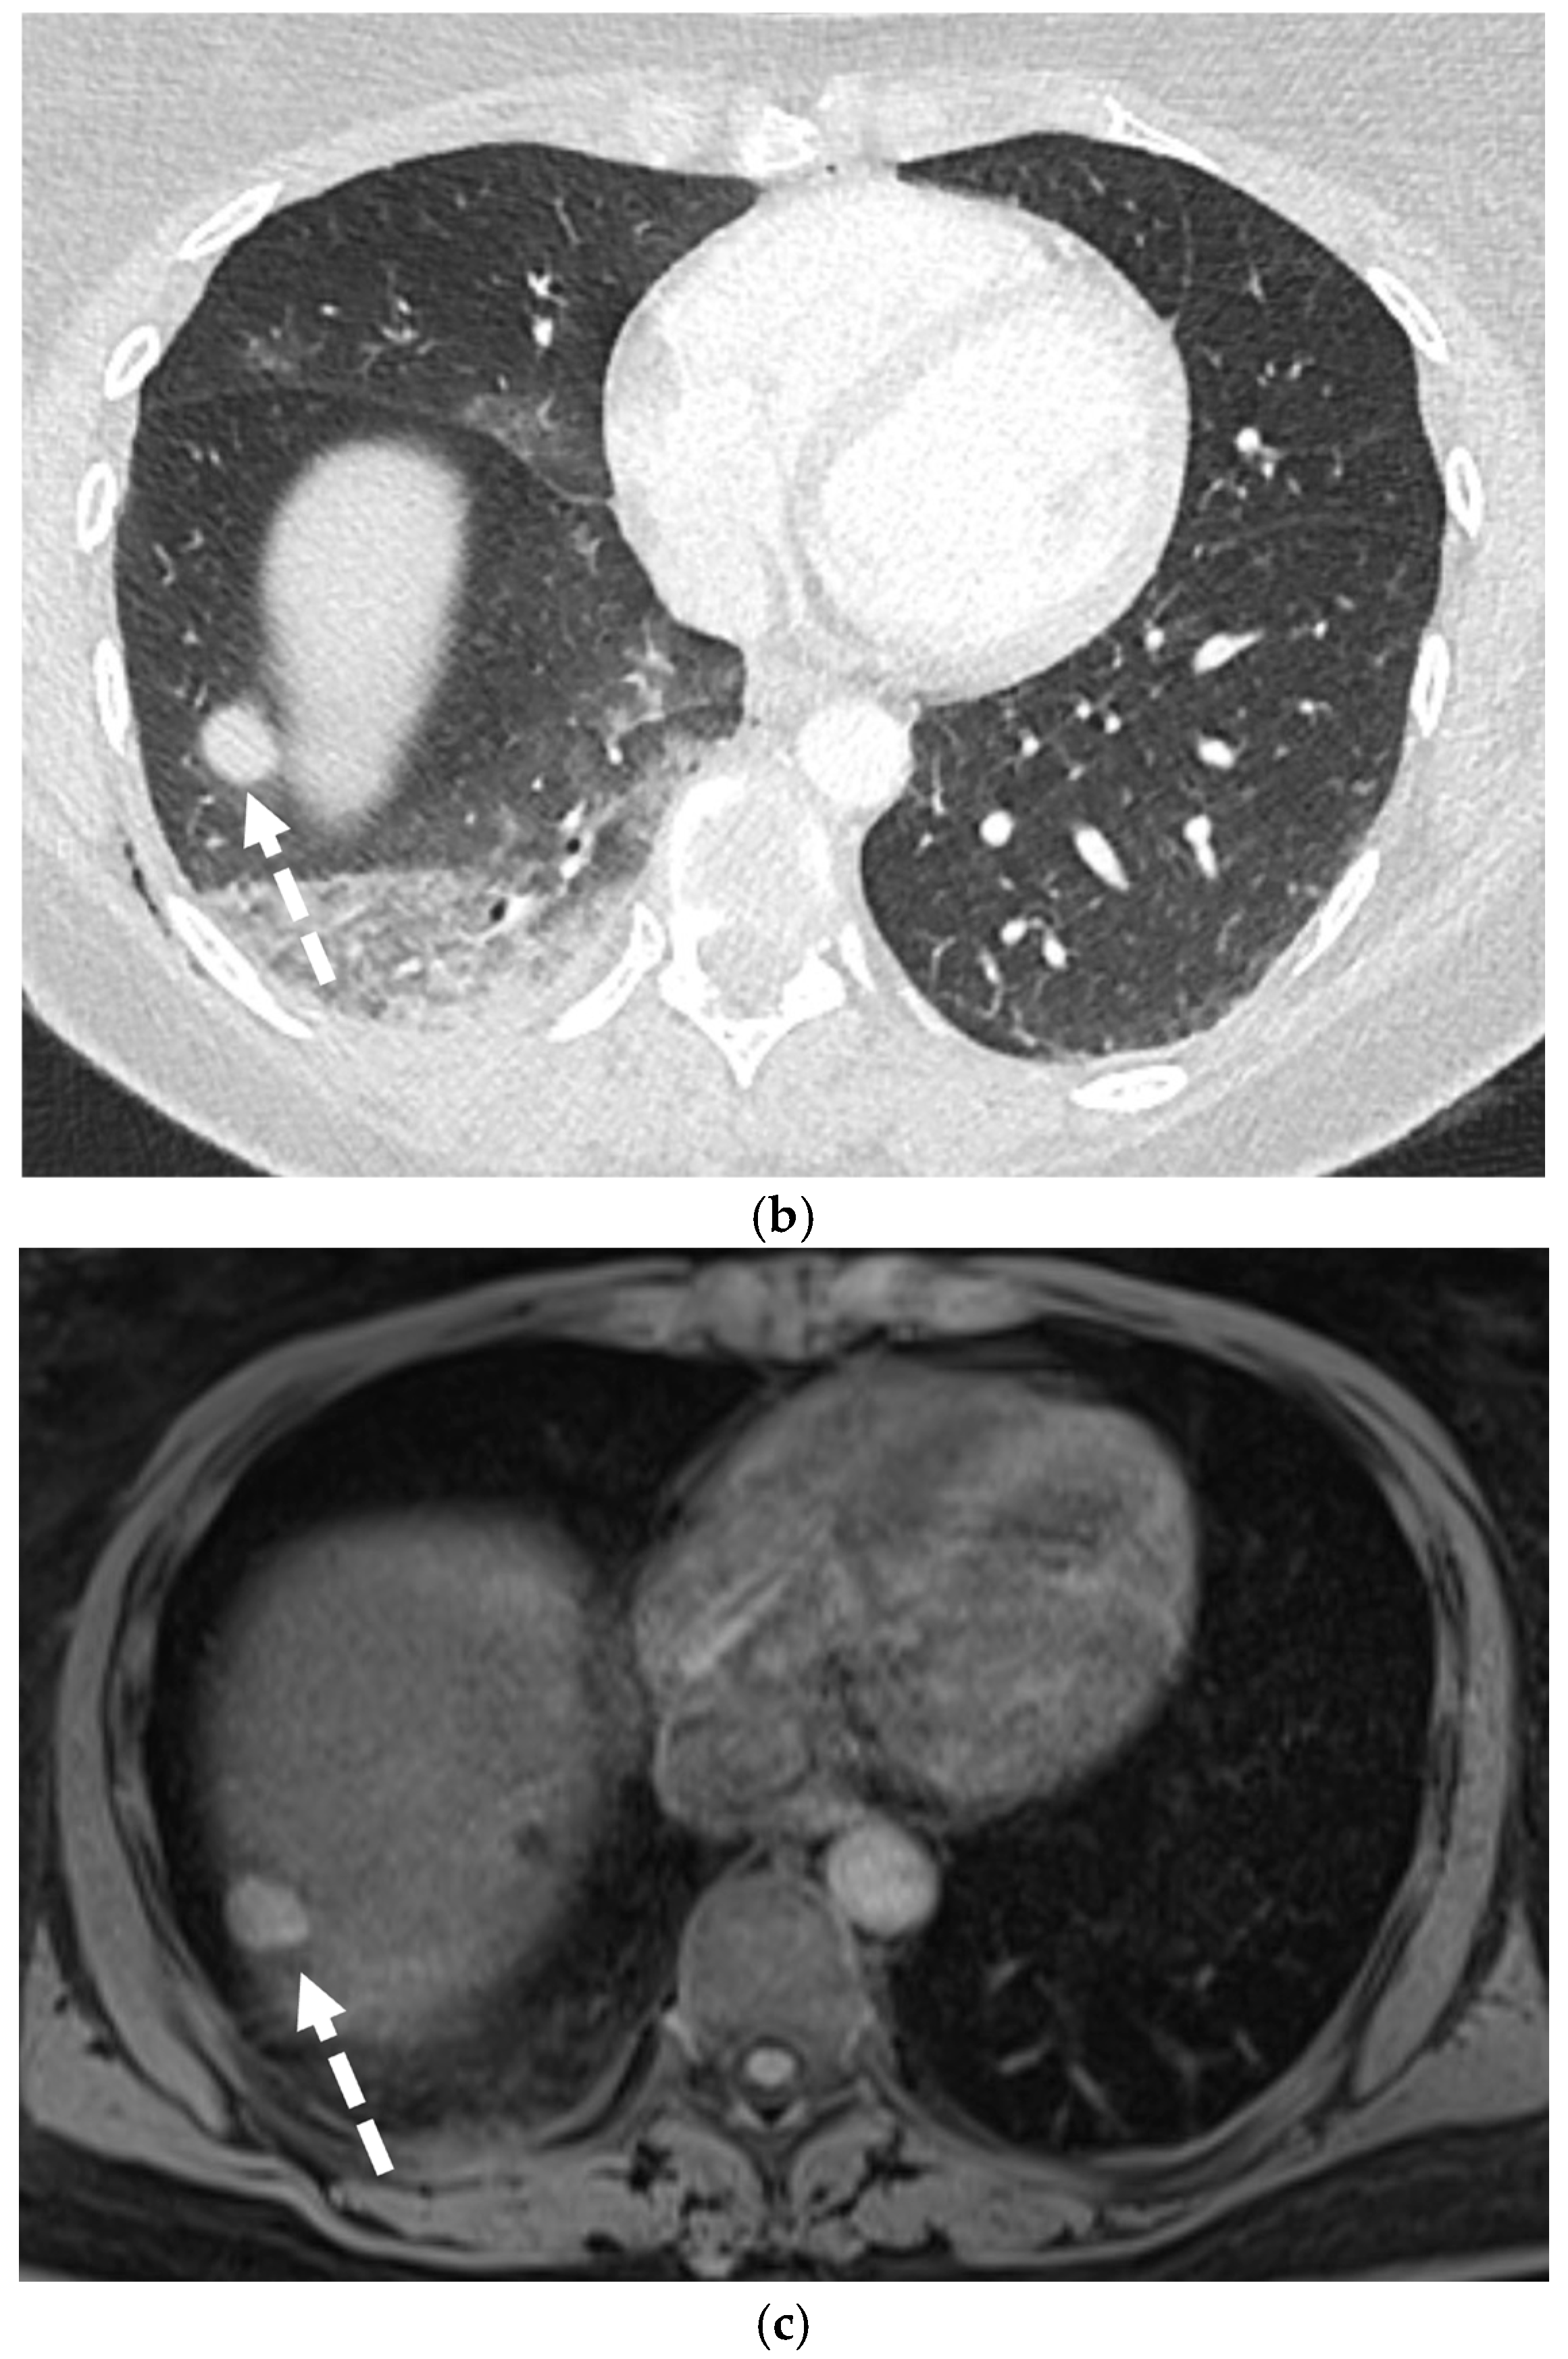

5.3. Malignancies

5.4. Interstitial Lung Diseases (ILDs)